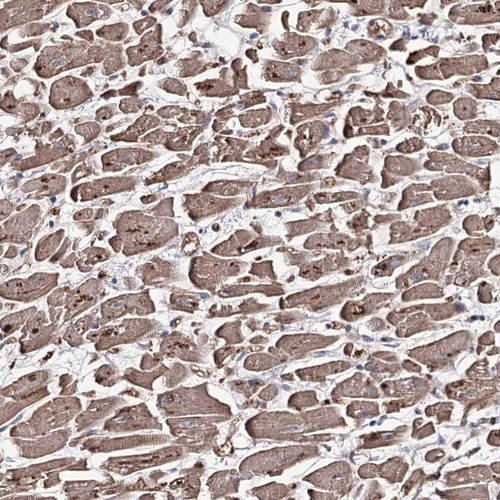

Immunohistochemical staining of human heart muscle shows cytoplasmic positivity in myocytes.